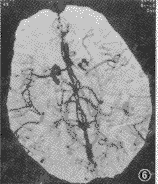

图6 左侧大脑中动脉栓塞CTA,可见左侧大脑中动脉自起始部变细,分支变少

脑血管成像示:(1)55例CTA均可清楚显示1~4级脑血管结构、Willis环和大脑前、中、后动脉主干及其分支情况。(2)脑动静脉畸形12例,其中枕叶3例,颞叶5例,额叶3例,顶叶1例。可见异常增粗迂曲的血管,9例血管呈团状,5例可见增粗的引流血管,5例部分血管有钙化,均可清楚地观察到畸形血管的位置和范围(图1)。(3)动脉瘤2例,清楚地观察到瘤体大小、位置、形态,以及与血管的关系(图2,3)。(4)脑肿瘤19例,其中9例脑膜瘤可见肿瘤邻近血管被推移或包裹,4例可见肿瘤表面有异常血管(图4)。4例胶质瘤和4例转移瘤可见瘤体呈不均匀强化,或不强化,周围有不同程度水肿,肿瘤附近血管被推移(图5);位于第4脑室的室管膜瘤和位于中颅窝蝶骨翼旁的三叉神经瘤可见瘤体呈不同程度强化,室管膜瘤有血管推移。(5)大脑中动脉及分支栓塞3例,2例大脑中动脉主干变窄、变细,远侧方血管变细、变少(图6);1例大脑中动脉顶后分支变细,变窄,远侧方血管较少;(6)脑挫裂伤及脑脓肿可见局部血管有不同程度推移,脑积水以两侧大脑前、中动脉抬高较为明显。